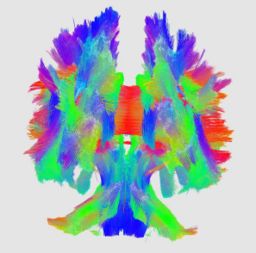

This project proposes a framework for quantitative analysis of DTI data. The framework uses the full tensor information for statistical analysis using the affine-invariant Riemannian metric for defining operations such as interpolation and averaging on tensors. Furtheremore, the results of tractography are used to provide a reference coordinate system the respresents the underlying structure of fiber bundles. The tract modeling framework includes a model both of the geometry of the fiber bundle and of the diffusion properties along the bundle. A new anisotropy measure called geodesic anisotropy (GA) is also included in the framework.

An initial test was performed by using the procedure on a set of images of healthy subject at age one year. The results of the tensor averaging are shown on the right. Tractography was also performed on the mean atlas image as shown.